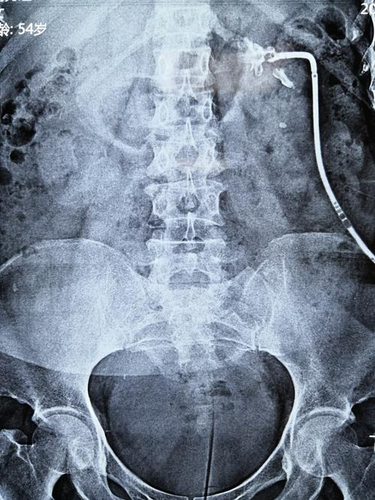

很多人去做x光检查的时候都会需要打造影剂。其实打造影剂的目的就是为了可以使影像的效果更加清晰而需要人体服用或者可以直接注入,但很多人会担心其副作用。那么到底造影剂等多久可以打呢?